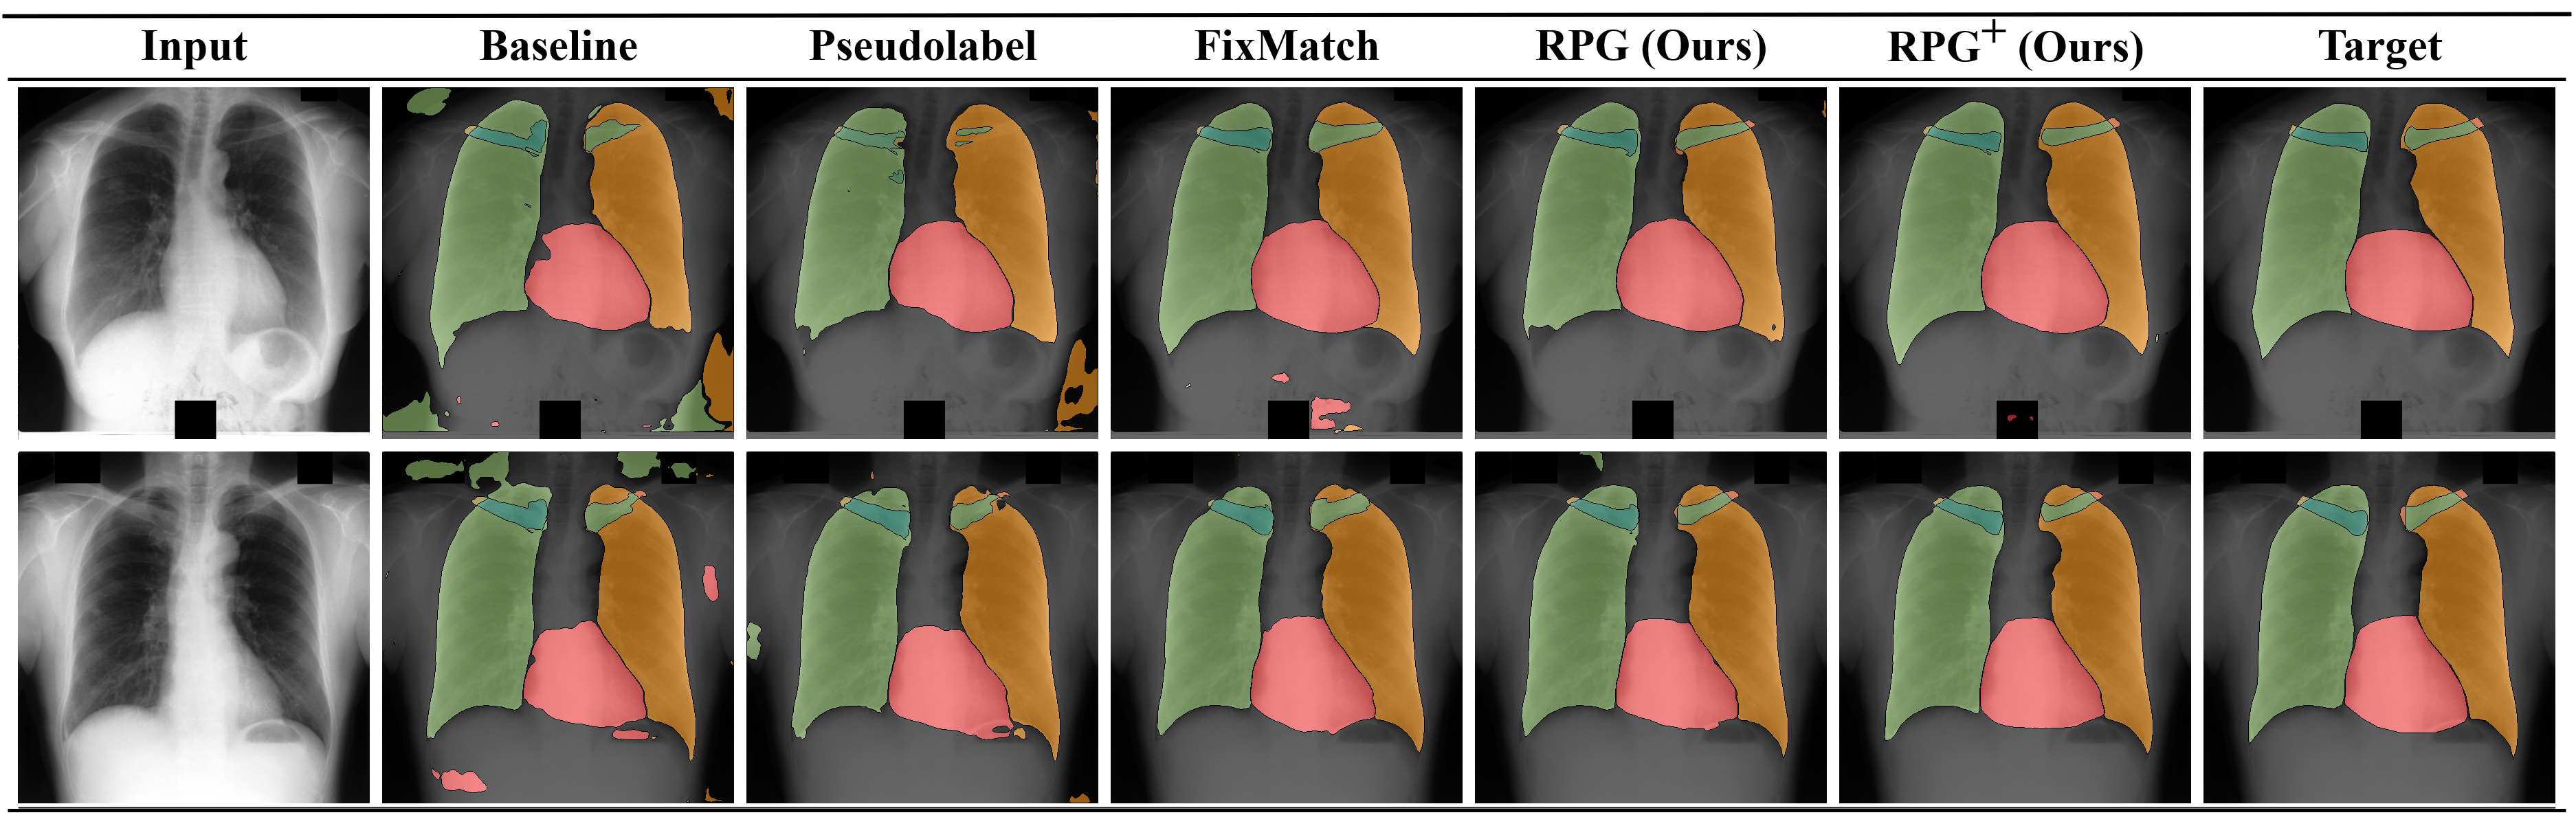

We further demonstrate the class-wise performance for three annotated samples on the top of Table 4. We see that the baseline as well as pseudo labeling struggle with less common classes like the clavicles. FixMatch shows considerable improvements for the classes with more annotated pixels, while the performance for the clavicles only slightly improves. also improves over the baseline for heart and lungs, but shows significant improvements for the difficult clavicles. Furthermore, combines the aspects of and augmentation-based consistency regularization, which noticeably improves all categories apart from the right clavicle with gains up to absolute over the baseline. We display segmentation predictions in Fig. 3, where class-wise shortcomings of the different methods become visible.